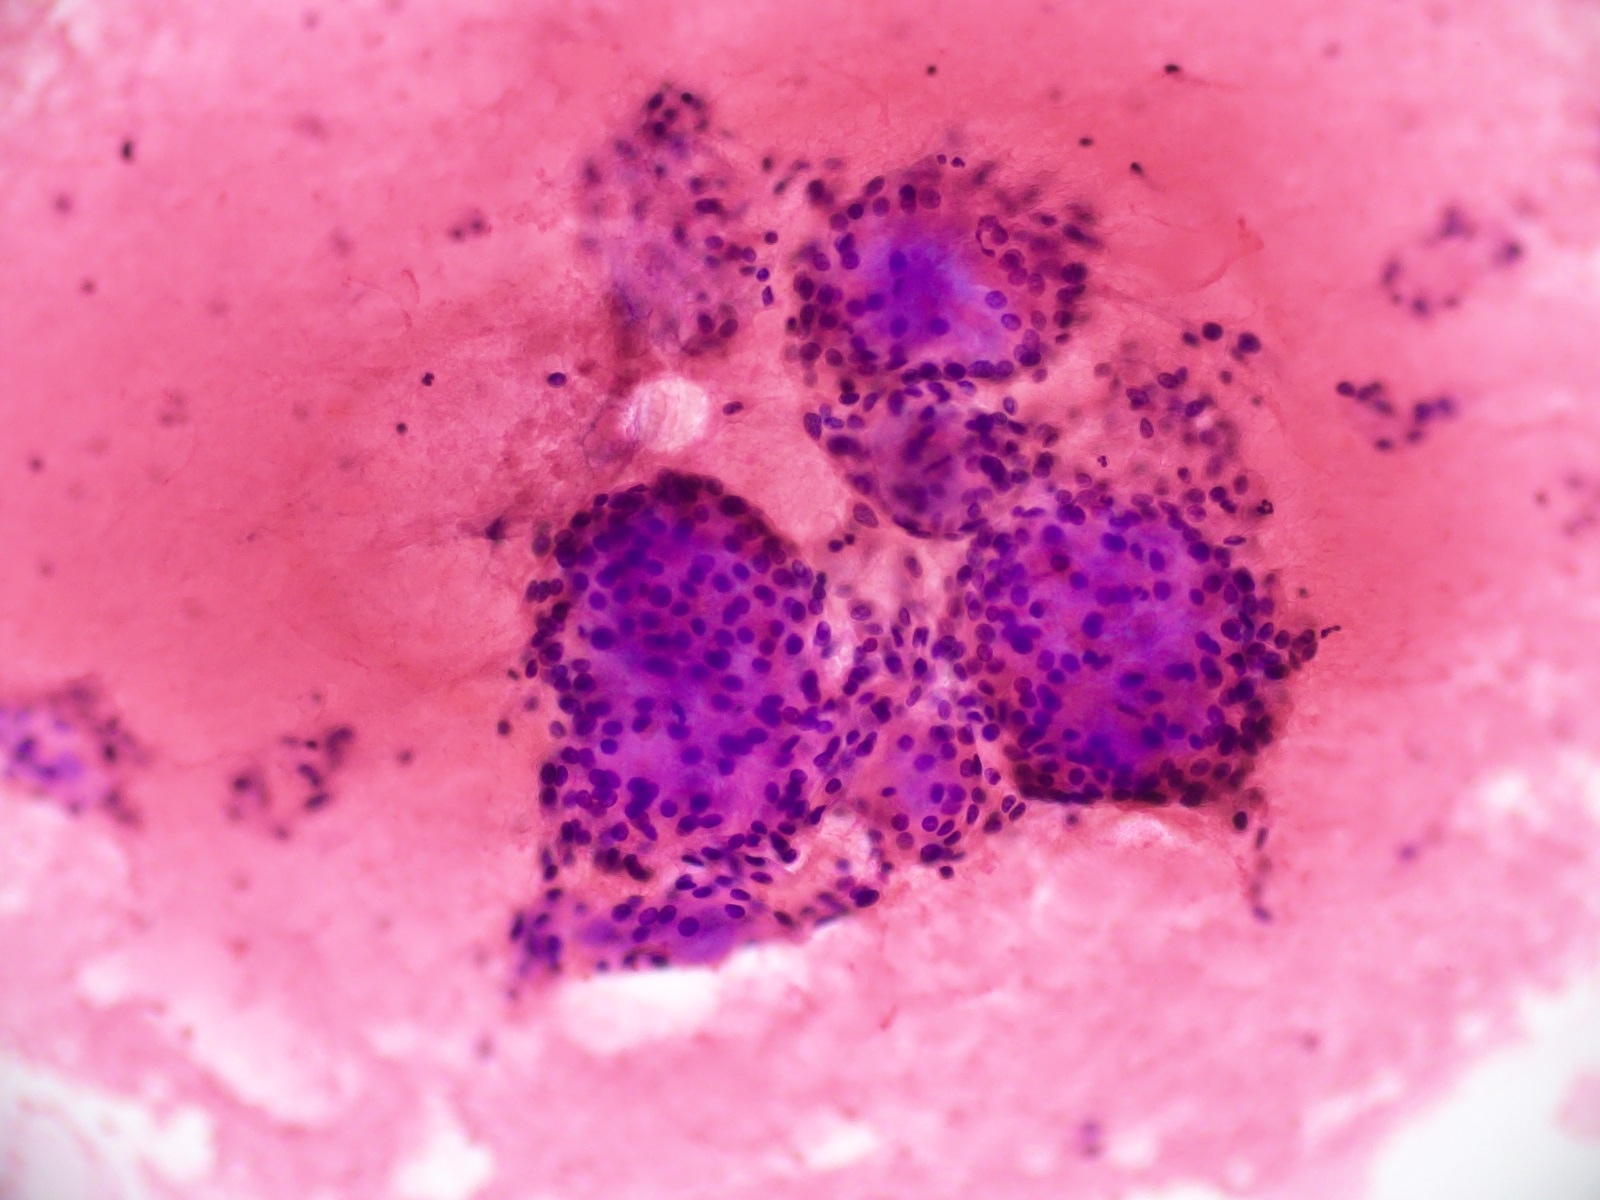

Cytology description

- Cytology usually recapitulates the histologic findings; myxoid matrix and cells show nuclear uniformity and process formation

- Epithelioid to spindle cells

- Arrangement of tumor cells around blood vessels forms papillary structures with perivascular myxoid change

- Tumor cells are arranged around myxoid microcysts

Cytology images